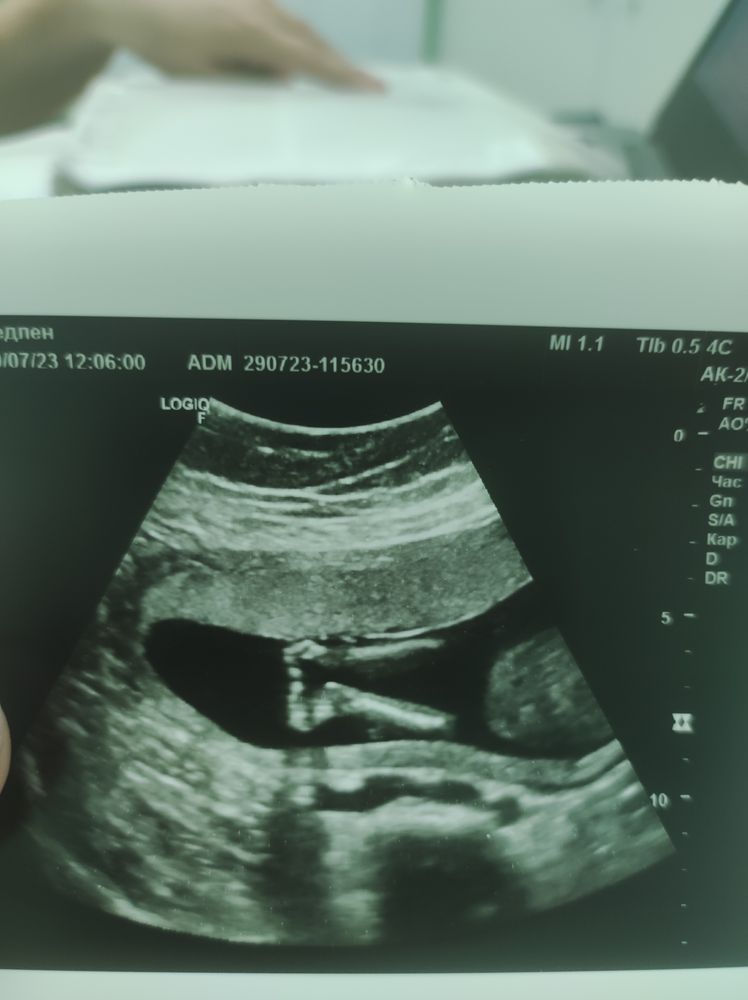

Первый скрининг 25 июля, срок день в день с моими расчетами. С ребенком все хорошо. Риски все низкие. Единственное, сахар 5,03, гинеколог сказала надо будет наблюдать и обязательно сдать ГТТ. Через неделю после скрининга выходит какой-то большой багровый сгусток. Паника. Я покупаю допплер, чтобы не бегать постоянно на УЗИ. С первого раза нахожу сердечко. Ритмичные частые четкие удары. Успокаиваюсь. Срок 13 недель. С этого дня чуть накрывает паника, я нахожу сердечко и успокаиваюсь.

На УЗИ больше не ходила до второго скрининга. Он был вчера. Перед ним все же накрыло паникой - "а вдруг что не так". Но все хорошо) Сегодня ровно 20 недель. Шевелюшки чувствую отчетливо. Допплер лежит уже без дела. Дай Боже, и дальше все будет хорошо. И родится здоровый мой сыночек в срок.